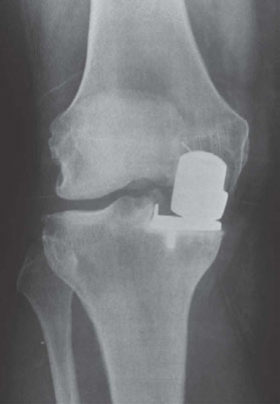

(Figure 3.4.) CANDIDATE : This is a weightbearing AP radiograph of left knee demonstrating moderate medial compartment osteoarthritis. The lateral compartment appears normal. There is a varus deformity of less than 10. I would like to take a history and examine the patient. The examination is focused mainly on localizing the tenderness, range of motion, if the varus deformity is correctable and stability of knee.

Figure 3.4

Anteroposterior (AP) radiograph knee. EXAMINER : The patient is fit and well, states that the pain is affecting his job and he would like to consider a surgical option. What would you offer him? CANDIDATE : The options of surgical management once conservative measures have failed include HTO, unicondylar knee arthroplasty or total knee replacement. Since this patient has a high-demand physical job, I would offer him HTO. EXAMINER : What are the prerequisites of HTO? CANDIDATE : A physiological age of < 60 years, fixed varus deformity < 15 or valgus deformity < 12, fixed flexion deformity of < 15, > 90 flexion. EXAMINER : Are you aware of any contraindication for HTO? CANDIDATE : The main contraindications are inflammatory arthropathy such as rheumatoid arthritis and psoriatic arthropathy, incompetent medial collateral ligament or ACL, large varus thrust with coronal subluxation of > 1 cm, severe OA of medial compartment or lateral compartment/PFJ and more than 20 of correction. Obesity is also a contraindication because valgus knee is poorly tolerated due to medial thigh contact. EXAMINER : The patient tells you that he has heard about partial knee replacement and is keen to consider the option. How do you proceed? CANDIDATE : I would explain to the patient that UKA is an option; however, I would not recommend UKA for this particular patient because the highly physically demanding job could result in accelerated wear of UKA. EXAMINER : So which patients would you offer UKA? CANDIDATE : The indications and prerequisites for HTO and